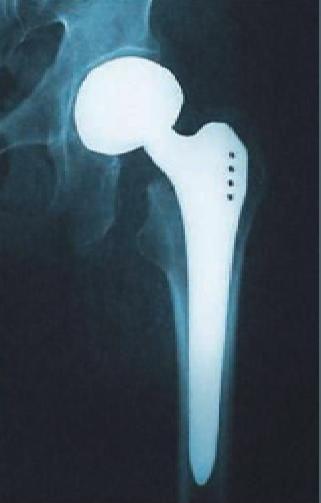

Protesi Anca

- Protesi Anca

L'anca è una delle articolazioni più grandi del corpo umano e sostiene il peso di tutto il corpo durante il cammino e la stazione eretta. Essa consiste in due parti: una sfera (la testa femorale) che è contenuta dentro una cavità (l'acetabolo). Una capsula (un manicotto fibroso attorno all'articolazione) e un legamento (il legamento rotondo) ne garantiscono la stabilità. Le superfici ossee sono ricoperte da cartilagine: un materiale estremamente liscio ed elastico che ne facilità lo scorrimento. Una sottile strato di tessuto (la membrana sinoviale) ricopre tutte le rimanenti superfici della camera articolare con la funzione di produrre il liquido sinoviale che rappresenta il liquido di lubrificazione dell'articolazione. Tutte queste componenti permettono all'anca di muoversi facilmente senza provocare dolore.